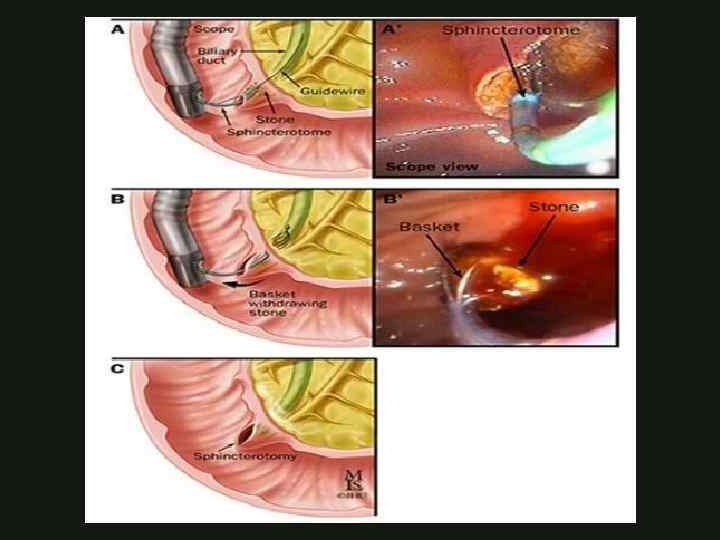

ЭНДОСКОПИЧЕСКОЕ ЛЕЧЕНИЕ ОСТРОГО ОТЕЧНОГО ПАНКРЕАТИТА Эндоскопическая папилосфинктеротомия Эндоскопическое стентирование ЭРХПГ КАФЕДРА ХИРУРГИИ МОСКОВСКОГО ФАКУЛЬТЕТА

ЭНДОСКОПИЧЕСКОЕ ЛЕЧЕНИЕ ОСТРОГО ОТЕЧНОГО ПАНКРЕАТИТА Эндоскопическая папилосфинктеротомия Эндоскопическое стентирование ЭРХПГ КАФЕДРА ХИРУРГИИ МОСКОВСКОГО ФАКУЛЬТЕТА